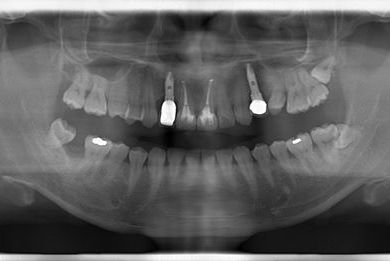

インプラントの症例写真 IMPLANT

抜歯即日スピードインプラント治療

| 性別/年齢 | 男性 / 36歳 | ||||||||||||||||||||||||||||||||

| 主訴 | 歯が折れているので、インプラントにしたい。 | ||||||||||||||||||||||||||||||||

| 治療方針 | 抜歯と同時にインプラント埋入を行い、治療期間を短縮する。 | ||||||||||||||||||||||||||||||||

| 治療内容 | インプラント2本(抜歯即日インプラント治療)、ジルコニアフレームオールセラミッククラウン1本、オールセラミッククラウン2本(セラミック用土台2本)、メタルボンドセラミッククラウン1本 | ||||||||||||||||||||||||||||||||